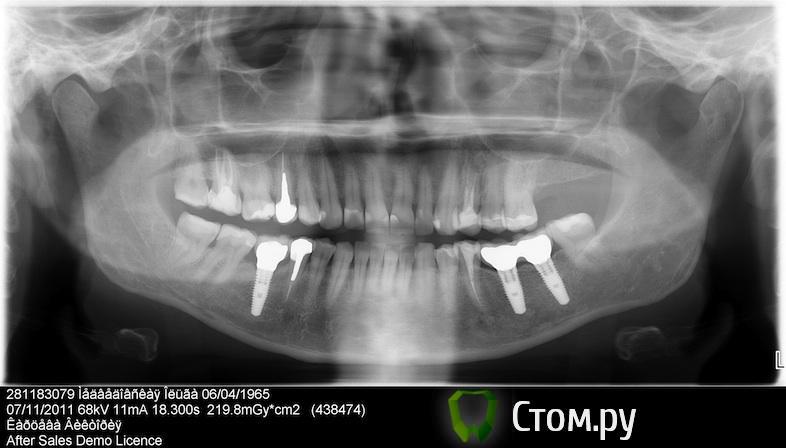

doctore Опубликовано 10 ноября, 2011 Поделиться Опубликовано 10 ноября, 2011 (изменено) ну эту картинку мы все видели ) хороший пример грамотных продаж ) Владислав, вы, как ментор Нобеля, наверняка сейчас активно начнете использовать новые имплантаты. Так вот, какая у вас будет форма абатмента на "нобель платформшифт" и "нобель ЦЦ" при установке Rp имплантата в дистальном отделе? Объем мягких тканей как раз таки легко создается десневой пластикой. Имплантолог,вероятно,крупно проигрался и задолжал.А тут две полные адентии откуда ни возьмись Согласен по поводу обьема и десневой пластики на 100%,но ведь в разумных пределах и при достаточной поддержке костной ткани(если она есть...Форма абатментов и результат,который я хочу видеть(это на Груви 4.3 и 5.0): Изменено 10 ноября, 2011 пользователем doctore Ссылка на комментарий

pit Опубликовано 11 ноября, 2011 Поделиться Опубликовано 11 ноября, 2011 (изменено) Имплантолог,вероятно,крупно проигрался и задолжал.А тут две полные адентии откуда ни возьмись Согласен по поводу обьема и десневой пластики на 100%,но ведь в разумных пределах и при достаточной поддержке костной ткани(если она есть...Форма абатментов и результат,который я хочу видеть(это на Груви 4.3 и 5.0): А Вы автор? И...... http://s42.radikal.ru/i096/1111/07/d9ba12a2a573.jpg Изменено 11 ноября, 2011 пользователем pit Ссылка на комментарий

doctore Опубликовано 11 ноября, 2011 Поделиться Опубликовано 11 ноября, 2011 (изменено) А Вы автор? И...... Пациентка одна-стороны разные.И хирургия и ортопедия мои. Изменено 11 ноября, 2011 пользователем doctore Ссылка на комментарий

pit Опубликовано 11 ноября, 2011 Поделиться Опубликовано 11 ноября, 2011 Пациентка одна-стороны разные.И хирургия и ортопедия мои.Очень даже симпатично. Исходные условия тоже хорошие. Десну формировали апикальным смещением и временными коронками?Нагрузили имплантаты одномоментно ли вторым этапом? В свете Ваших приципов идеализации лечения, этот кейс выглядит не завершенным, позвольте пульнуть камушек в Ваш огород))))))))))))))))))))))) Почему Вы не сделали интрузию 26 зуба и не установили имплант в позицию 27 зуба? ( спрашиваю как ортопед) А вобщем работа понравилась и врачебное, и техническое исполнение Ссылка на комментарий

Большой Зеленый Опубликовано 11 ноября, 2011 Поделиться Опубликовано 11 ноября, 2011 Почему Вы не сделали интрузию 26 зуба и не установили имплант в позицию 27 зуба? ( спрашиваю как ортопед) там 38 уже удалять надо на фото видно ,что под 27 места уже не остается давно антагониста нету .. да и гребень там узковат... Ссылка на комментарий

Bobby Опубликовано 11 ноября, 2011 Автор Поделиться Опубликовано 11 ноября, 2011 Пациентка одна-стороны разные.И хирургия и ортопедия мои. Владислав, подскажите, а зачем соединяли 3.6 и 3.7 ? Ссылка на комментарий